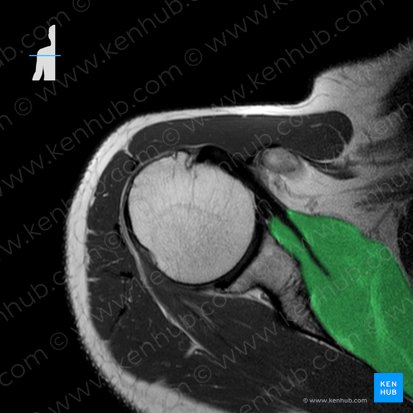

From the costal surface of the scapula, the muscle fibers course laterally, gradually narrowing towards a round tendon that courses towards the proximal humerus. The large subscapular bursa that communicates with the shoulder joint separates the subscapularis tendon from the neck of the scapula. The tendon then inserts to the lesser tubercle of humerus and anterior part of the articular capsule of the glenohumeral joint. As it approaches the humerus, the tendon is continuous with the tendon of the teres major muscle. In fact, these two muscles share the same innervation and actions, and are often considered as a functional muscular unit.

The posterior surface of the muscle’s tendon is blended with the fibrous capsule of the glenohumeral joint, and is continuous with the tendons of supraspinatus, infraspinatus, teres minor and long head of triceps brachii. These tendons together comprise the rotator capsule around the shoulder joint.